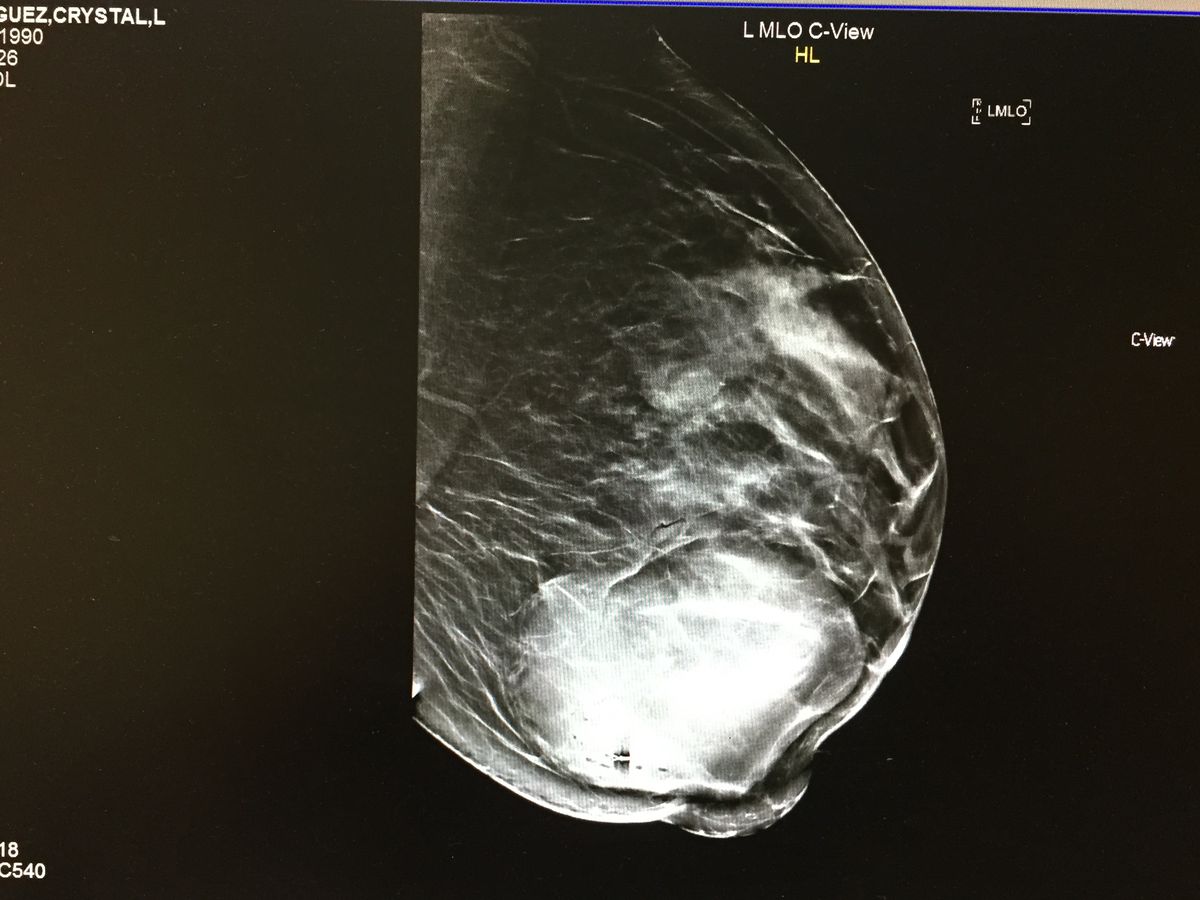

The reason why I am trying to raise this money is because my insurance is only covering some of the payment towards the surgery I will be getting done. The surgery itself cost $6200 As you can see in the picture it's pretty big (the round white spot) & because of that it's costly. No it's not cancerous, they tested it & it came back negative. THANK GOD! But this is painful to me & I was a told if I do not get it removed the tumor will continue to keep growing & my left breast will just get bigger. As for all my friends & family they know for some one who is really short "5ft" , I have some pretty big breasts. It's bad enough that I deal with lower back & shoulder pains as it is. This tumor is just adding more weight, and it's so uncomfortable to run, walk fast or even sleep. So I'm asking for help, so I can get this procedure done asap. I appreciate every little bit. Thank you.